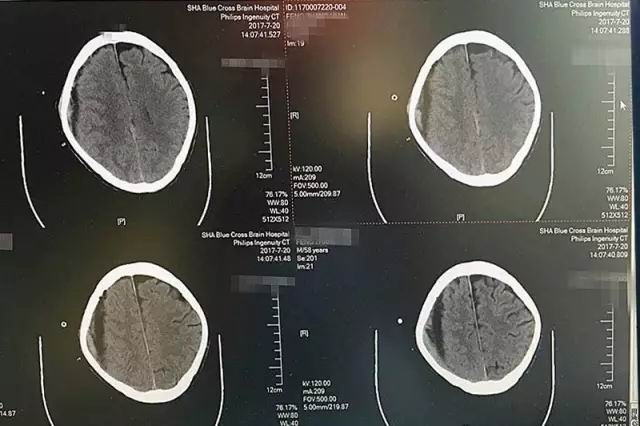

第一天,术中引流出暗红色血液120毫升左右,脑CT影像显示,血肿大部分被吸收。

第二天,又引流出90毫升暗红色血液,术后CT显示血肿基本清除干净。

第三天,血肿顺利被清除,就像工兵搬走了地雷,警报解除。

红圈处为高密度引流管,进入颅内约1.2厘米,后部为放射状伪影

就这样,历经三天,72小时,李振并主任成功地为老冯解除了脑出血的威胁,平稳又娴熟地将他大脑右半球的陈旧性出血基本清除干净。术后仅三天,我们的老冯就能下地走路了!

患者术后CT影像显示:血肿基本被吸收